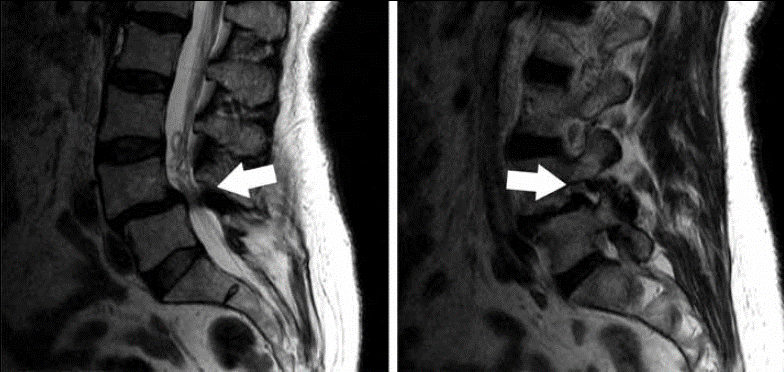

نوبت دهی | ام آر آی ستون فقرات و اطلاعات درباره آن

علت انجام ام آر آی ستون فقرات چیست درد کام آر آی ستون فقرات از میدان مغناطیسی قوی و امواج رادیویی برای تصاویر با...